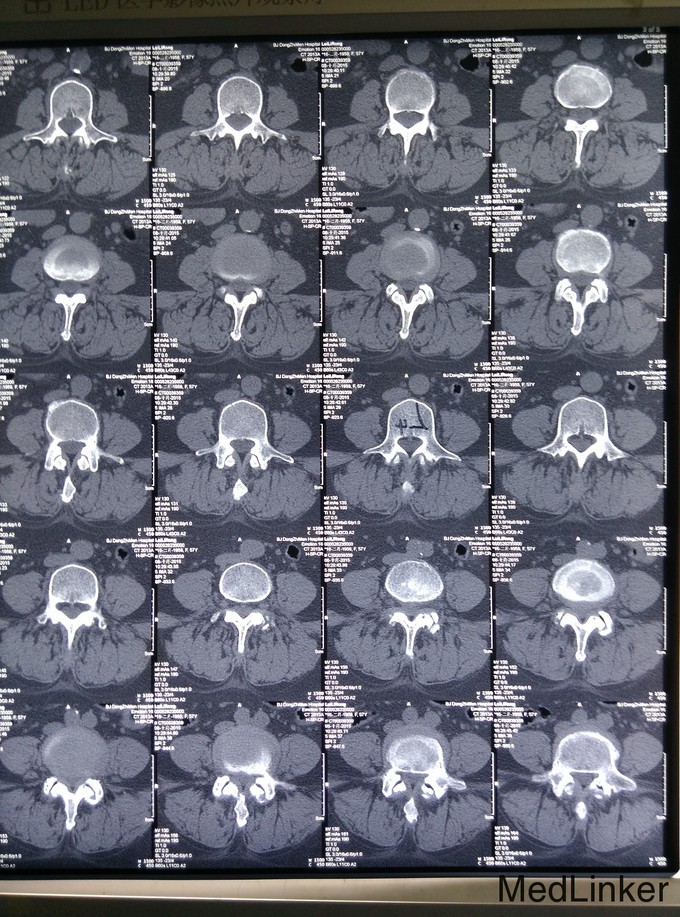

查体:脊柱生理弯曲存在,无腰椎侧突畸形,腰4-骶1椎旁压痛和深部扣击痛(+),腰部活动稍受限,直腿抬高试验双侧阴性,双下肢浅感觉无明显减退,双下肢肌力4级,双下肢膝反射和踝反射稍减弱,髌阵挛、踝阵挛未引出。病理反射未引出,肛周浅感觉正常,肛门反射正常。 腰椎CT及腰椎MRI示:L4-5、L5-S1椎间盘突出,椎管狭窄,黄韧带肥厚,相应硬膜囊受压。

诊断:腰椎管狭窄症、腰椎间盘突出、腰椎骨关节病 治疗:入院后完善相关检查,无明显手术禁忌症,于手术室全麻下行腰4-5、腰5-骶1椎板切除、椎管减压、椎弓根内固定术,